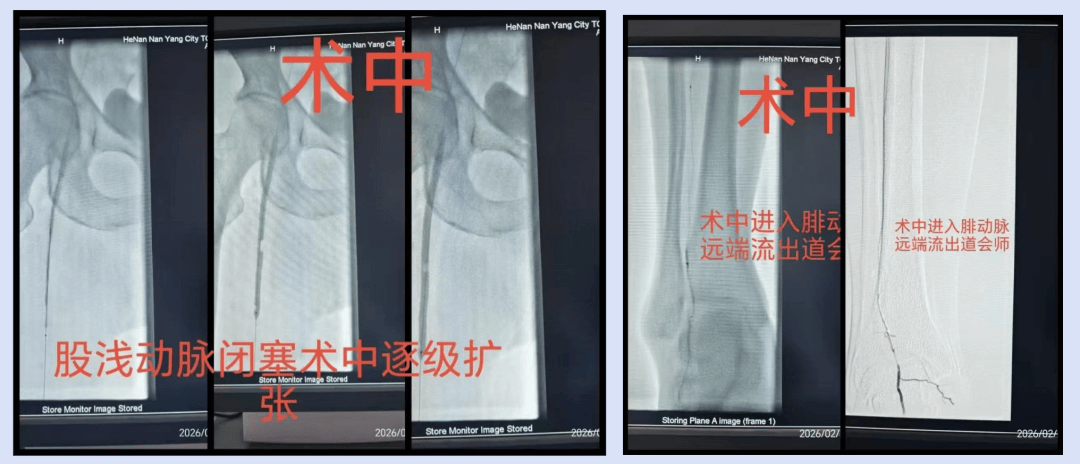

DSA示: 下肢动脉硬化闭塞;股浅动脉起始处及以下全程闭塞;膝下三支动脉全部闭塞。右下肢肢体仅有腓动脉远端显影,右足足部动脉显影惨淡。属于TASC II D型病变(长段极复杂病变)。

1.先用导丝精准开通闭塞血管,打通血运通道;

2.再用球囊逐级扩张血管,做好管腔准备,将狭窄、闭塞的血管撑开;

3.针对股浅动脉中下段限流性夹层,选择性置入支架,保障血管管腔通畅。

整个手术微创、精准,术后造影显示,患者右下肢动脉血运即刻恢复,原本的疼痛症状瞬间消失,为后续足部溃疡的修复奠定了关键基础。